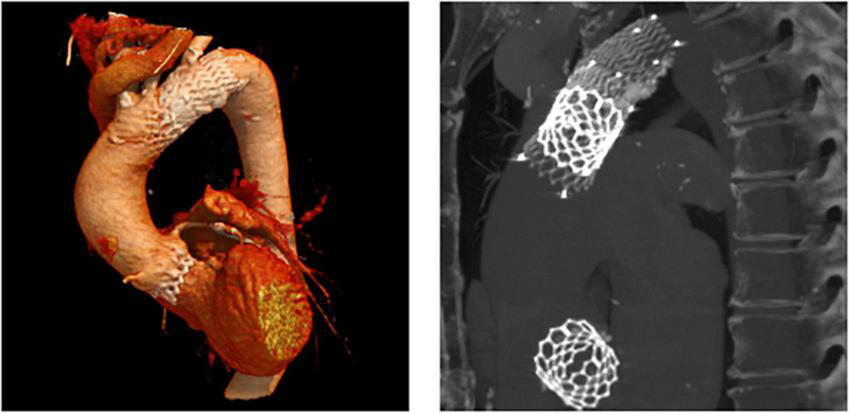

In patient 8, the embolized valve remained in the descending aorta. In this particular case, the snare used to pull the embolized Evolut R further into the ascending aorta (to avoid coronary obstruction) was stuck within the valve frame. The bent Evolut PRO was eventually pulled into the descending aorta where the snare could be liberated (Figure 4). Corresponding to the overall lower incidence of TVEM during TAVI using a balloon-expandable valve, only two patients underwent CT follow-up after embolization of an Edwards Sapien 3 caused by loss of capture during implantation. In patient 1, the embolized valve remained in the aortic root and was secured by valve-in-valve-implantation of a second Sapien. In patient 7, management of the TVEM was complicated by a combination of an aneurysm of the ascending aorta and a narrow, calcified arch. Consequently, the embolized valve could neither be implanted into the wide ascending aorta nor withdrawn into the descending aorta. Instead, it was gently pulled back by the semi-inflated delivery balloon as far as possible into the proximal aortic arch and affixed by two self-expanding stents (Figure 5).

FIGURE 4

CT images of a patient with embolization of an Evolut PRO. In this case (patient number 8 from Table 5), the snare used to pull the embolized Evolut PRO further into the ascending aorta was entangled in the valve frame. The bent Evolut PRO was eventually pulled into the descending aorta where the snare could be liberated.

FIGURE 5

CT images of a patient with embolization of a Sapien 3. CT follow-up of patient number 7 (Table 5). After embolization due to loss of capture during implantation, the embolized Edwards Sapien 3 was pulled back into the proximal aortic arch by the semi-inflated delivery balloon and affixed using two self-expanding stents.